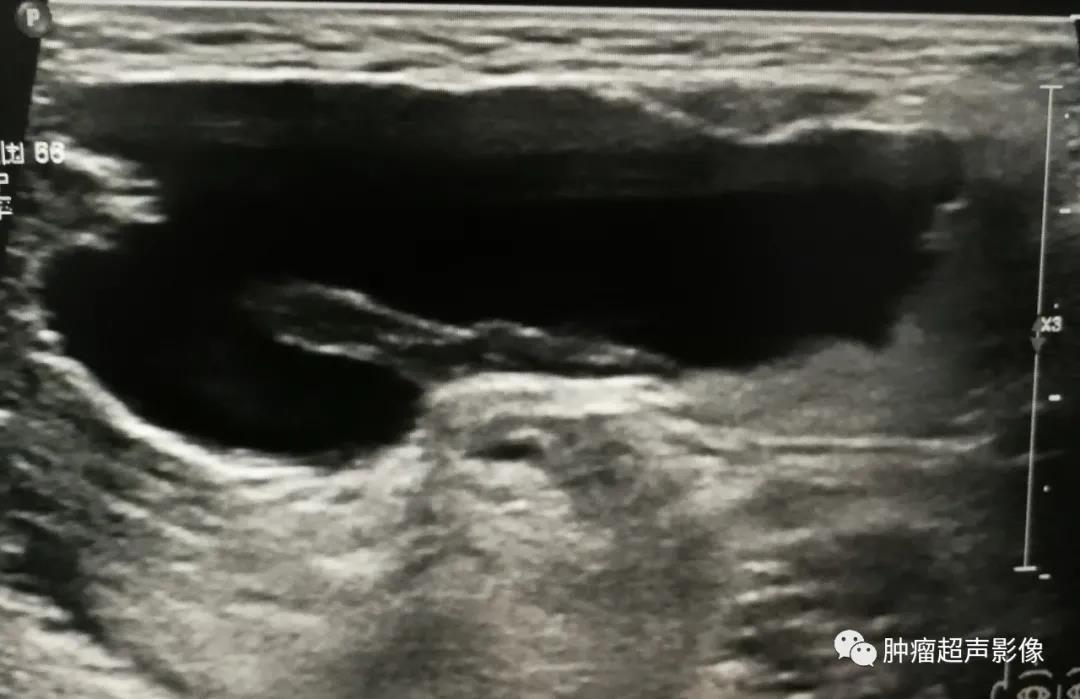

手术证实的口外型舌下腺囊肿:颌下形态欠规则无回声,大部分边缘光整,口底侧局部边缘毛糙、无明确的包膜,透声欠佳,无血流,比较容易误诊。